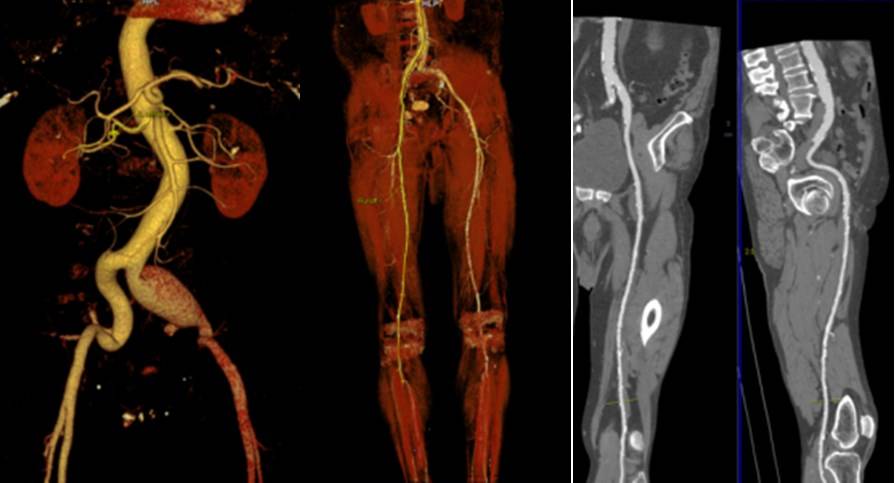

Αξονική Αγγειογραφία (CTA)

Η Αξονική Αγγειογραφία (CTA) είναι μια ιατρική εξέταση που χρησιμοποιεί τεχνολογία της υπολογιστικής τομογραφίας (CT) για να παράγει λεπτομερείς εικόνες των αγγείων.